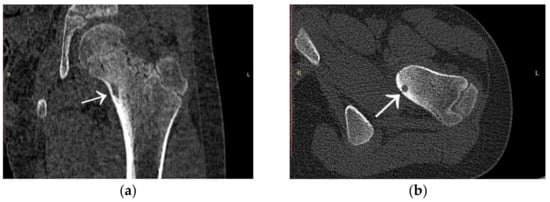

3.1. Case 1: OO Masking as Femoroacetabular Impingement (FAI)

3.6. Case 6: OO Masking as Chronic Hip Arthritis

4.3. Presentation of Osteoid Osteoma Localised Intraarticularly